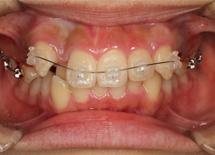

矯正歯科治療の中でも最もオーソドックスな治療法が、表側矯正(ワイヤー矯正)です。この表側矯正は歯にブラケットという装置を取り付け、そこにワイヤーを通して歯に力をかけながら、少しずつ歯を移動させて歯並びを整えていくという治療方法です。表側矯正(ワイヤー矯正)は最も適応範囲の広い治療方法です。

永久歯列の治療で、歯を動かすためにワイヤーの力を利用して歯の移動を行う装置をマルチブラケットアプライアンスと呼びます。

セルフライゲーションブラケット装置(デーモンクリア)、歯の裏側に装着するカスタムメイド型リンガルブラケット等の種類があります。ワイヤーを使わないものとして、マウスピース型矯正装置(インビザライン)があります。これは半透明なマウスピースを1日20時間以上装着することで歯を移動します。

デーモンクリア

リンガルブラケット